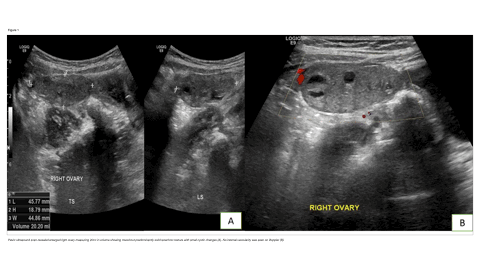

Bahrain - Pediatric Ovarian Torsion at Two Years of Age: A Rare Gynecological Emergency

https://doi.org/10.59667/sjoranm.v26i1.20

Mujahed Abdul Sattar Raheem1, Arshed Hussain Parry*1, Hussam Hassan Ismail1, Wael Hamed Ibrahim1, Martin Corbally1

¹Department of Radiology, King Hamad University Hospital, Busaiteen, Al Muharraq, Bahrain

This case report discusses the diagnosis of pediatric ovarian torsion including risk factors, symptoms, imaging modalities, and surgical diagnostics to improve diagnosis and shorten time to treatment. In addition, this case supports the use of laparoscopy for diagnosis of ovarian torsion if indicated by clinical suspicion and supplemental imaging studies.